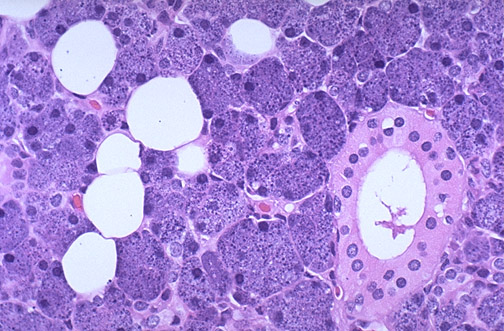

At high magnification, the normal parotid gland has acini composed of

serous cells

with abundant darkly staining granules. There are admixed

fat cells

, and some

ducts

lined by cuboidal epithelium are present.